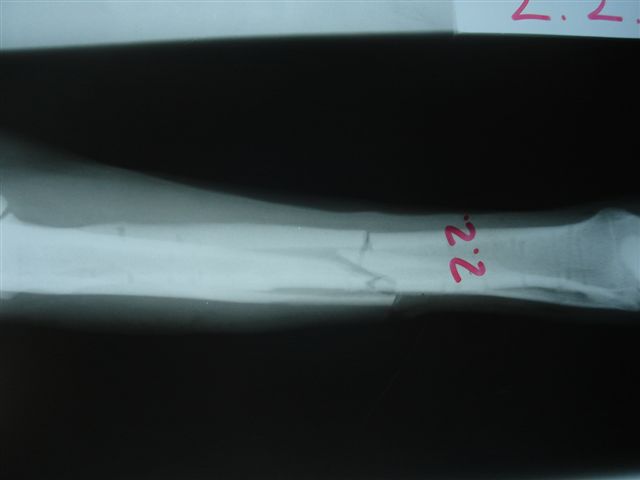

Fijación Externa

Casos prácticos alumnos.